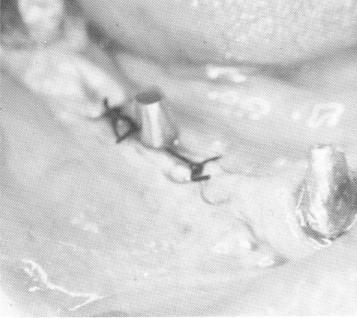

Fig. 11-62. The mandibular blade centered between natural abutments.

Fig. 11-60. A double-posted blade was used in the fairly long span to produce ample support.